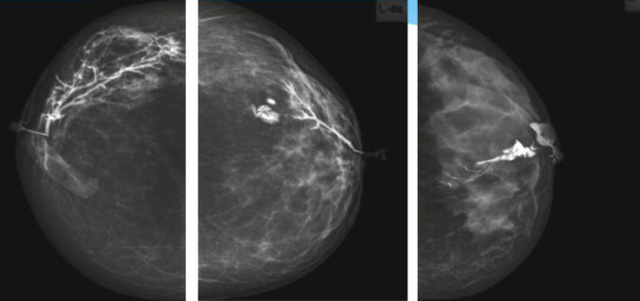

乳腺導管內乳頭狀瘤分為以下兩個,位於乳暈區大導管的中央型乳頭狀瘤,起源於末梢導管小葉單位的外周型乳頭狀瘤。外周型乳頭狀瘤常常沒有明顯的的臨床表現,常因X線或乳腺秋葵视频APP下载安装檢查發現。重點要關注的是中央型乳頭狀瘤,發生於任何年齡的女性,以40~50歲者居多。它表現為:單側乳頭溢液,特別是血性溢液少數病人可在乳暈區觸及腫塊。從病理學上麵講表現為導管上皮和間質增生形成有纖維脈管束的乳頭狀結構。這是它一個病理學上的表現。它的超聲表現為:病變導管囊狀擴張呈無回聲,內可見乳頭狀低回聲或中等回聲。乳暈處的導管擴張,管腔內可見邊界清楚的,低回聲實性結節。外周型導管內乳頭狀瘤可,表現擴張為為低回聲的實性結節,CDFI:部分腫瘤可顯示為軸心性的看到血流信號。乳腺增生症:可見導管擴張,內無乳頭狀實性回聲,導管內乳頭狀癌:囊內乳頭狀癌病變較大,不規則,厚基底,血流豐富。以囊性為主的混合回聲,形態不規則,內見實性低回聲實性低回聲可見少量血流,病理為囊內乳頭狀癌。

乳腺秋葵视频APP下载安装檢查的價值在哪裏呢?它可以檢查發現乳暈周圍的各種病變,對於單側乳頭溢液、血性溢液的患者,超聲是首選的影像學檢查方法。注意:導管內乳頭狀瘤可合並不典型增生或,導管內乳頭狀癌,手術前懷疑時候,就應該手術切除而不是用微創手術。